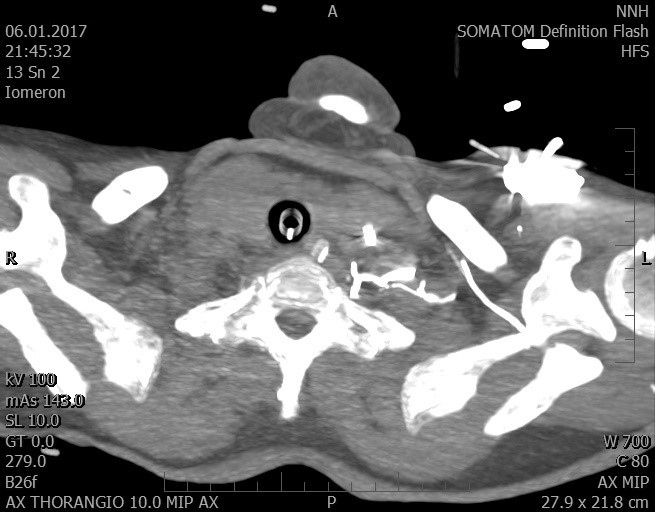

Video 2 - Echokardiograficky byla zjištěna těžká dysfunkce dilatační levé komory s nezvětšenou pravou komorou.Pro nejasnou příčinu zástavy jsme provedli i vyšetření výpočetní tomografií (CT), které vyloučilo plicní embolizaci (série 1 - soubory na konci článku). V den přijetí při přetrvávající oběhové nestabilitě byla nemocná opakovaně defibrilována pro fibrilaci komor se stabilizací rytmu po podání amiodaronu a mesocainu. Dle hemodynamických měření se jednalo o těžký kombinovaný šok. Vstupní laboratorní vyšetření bylo bez větších pozoruhodností. Posléze jsme doplnili anamnézu od příbuzných a zjistili, že pacientka užila do dvou hodin před srdeční zástavou první tabletu amoxicilinu na lehký respirační infekt. Při nevýtěžnosti vstupních vyšetření a nových anamnestických informacích jsme doplnili 14 hodin po kolapsu vyšetření koncentrace tryptázy v séru, která byla extrémně zvýšena (tabulka 2), což nás vedlo k podezření na anafylaxi.